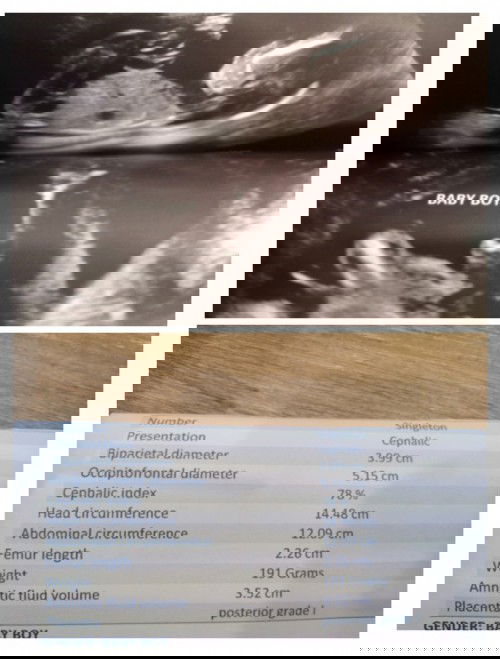

Baby boy na po ba talaga yung ganitong ultrasound 🤗 pero next month po mag papa ultrasound po ulit ako for confirmation 17weeks and 4days #1stimemom #firstbaby

I think yes, may lawit kasi